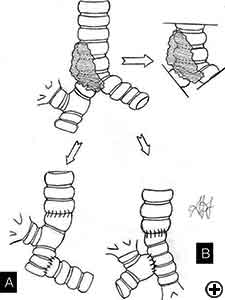

In isolated carinal resection and reconstruction, applicable for centrally located, low grade and small tumors (Video 8), the right and left main bronchi can be medially sutured to create a new carina, that is subsequently anastomosed to the distal trachea (Figure 2C and Video 9). A less common technique provides the resection of the carina followed by an end-to-end anastomosis between the left main bronchus and the trachea, followed by anastomosis of the right main bronchus to the lateral, cartilaginous wall of the trachea, paying attention to stay at least 2 cm above the first anastomosis (Figure 6). When more advanced tracheal involvement is present, two alternative techniques may be used to avoid excessive tension: an end-to-end anastomosis between the right main bronchus and the trachea, followed by anastomosis of the left main bronchus to the lateral, cartilaginous wall of the bronchus intermedius or an end-to-end anastomosis between the left main bronchus and the trachea, followed by anastomosis of the right main bronchus to the lateral, cartilaginous wall of the left main bronchus (Figure 7). In all of cases a wide hilar release is mandatory to reduce tension on the anastomoses.